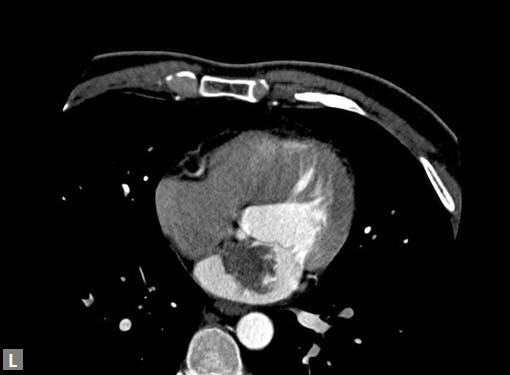

Any part of aorta can get affected by aneurysms. Focal

dilations can be saccular or fusiform. Atherosclerosis is

the most common cause. Tubercular and other infective

aneurysms, traumatic ones are also uncommonly seen. Size

of the aneurysm, proximity to origin of main vessels, relation

with branching and bifurcation, presence of mural thrombus

are the critical information sought on CT.

Contained leak, rupture are the feared complications.

Aortoenteric fistula is a rare but potentially catastrophic

complication. Aneurysmal dilation is common in ascending

aorta (Figs 19W to Y).

CT is also useful in surveillance of diagnosed aneurysms.

Figs 19A to Y (A to C) Scannogram (A), plain (B) and contrast study (C) show partial anomalous pulmonary venous connection; (D to F) Heterotaxy; (G) Aortic occlusion; (H and I) Aortic stents; (J) Aortic dissection with ‘Benz’ sign due to second dissection within the true lumen; (K, L and M) Aortic dissection with thrombus in pseudolumen following catheter angiogram; (N) Aortic dissection involving common carotid arteries and subclavian artery; (O, P, Q and R) Aortic dissection with right renal artery arising from true lumen and left renal artery from false lumen; (S, T, U and V) Stanford B dissection with extension Y to iliac vessels; (W to Y) Aneurysmal dilation of ascending aorta